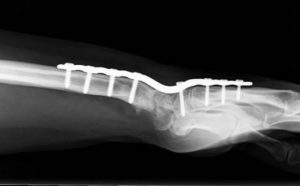

Es posible que las articulaciones restantes de la muñeca pudieran desgastarse con el tiempo tras esta operación, ya que quedan como resultado menos articulaciones para distribuir las cargas de la muñeca.  Si esto ocurriera en un futuro, todavía se podría recurrir a la fusión o artrodesis total de la muñeca (Figura 2).

Figura 2 - Artrodesis total de muñeca con placa y tornillos.